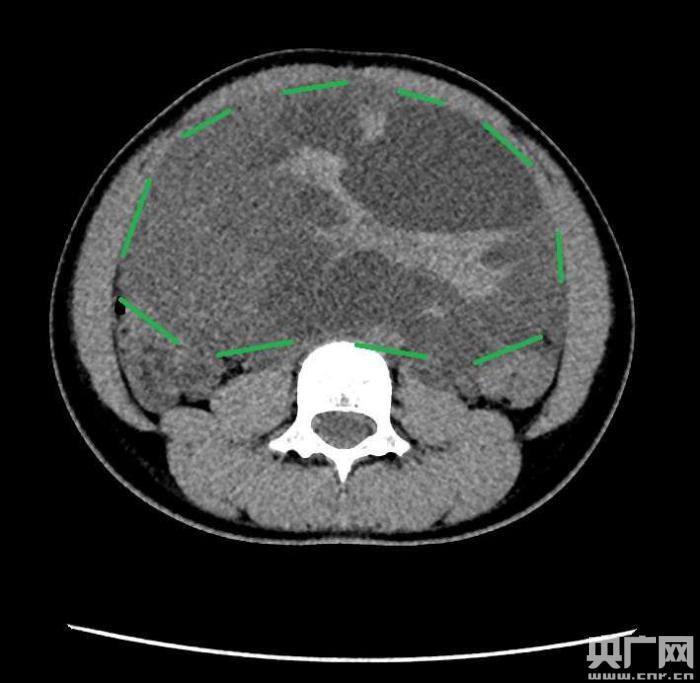

入院后,普外一科肖東主任向家長詢問了病史,仔細(xì)進(jìn)行了體格檢查,并完善腹部CT。CT結(jié)果提示,孩子的大部分腹腔、盆腔被一個(gè)巨大的腫瘤占據(jù),腸道、血管和腎盂都受到了不同程度的壓迫。從CT上看,腫瘤很可能起源于左側(cè)的卵巢。

手術(shù)中發(fā)現(xiàn),小琪腹中的腫瘤體積巨大,大小約為25×20×15厘米,表面光滑,來源于左側(cè)卵巢。醫(yī)生們首先將其與周圍的組織小心剝離,然后將這個(gè)占據(jù)孩子腹腔、盆腔大部分的巨大包塊完整切除,切除腫瘤后還重建了左側(cè)卵巢。剖開瘤體,發(fā)現(xiàn)瘤體為囊性及實(shí)性混合組成,瘤體內(nèi)部充盈著粘液狀的液體,重量達(dá)到了3000克。術(shù)后小琪病情穩(wěn)定,測量腹圍從術(shù)前的72厘米減小到了62厘米。